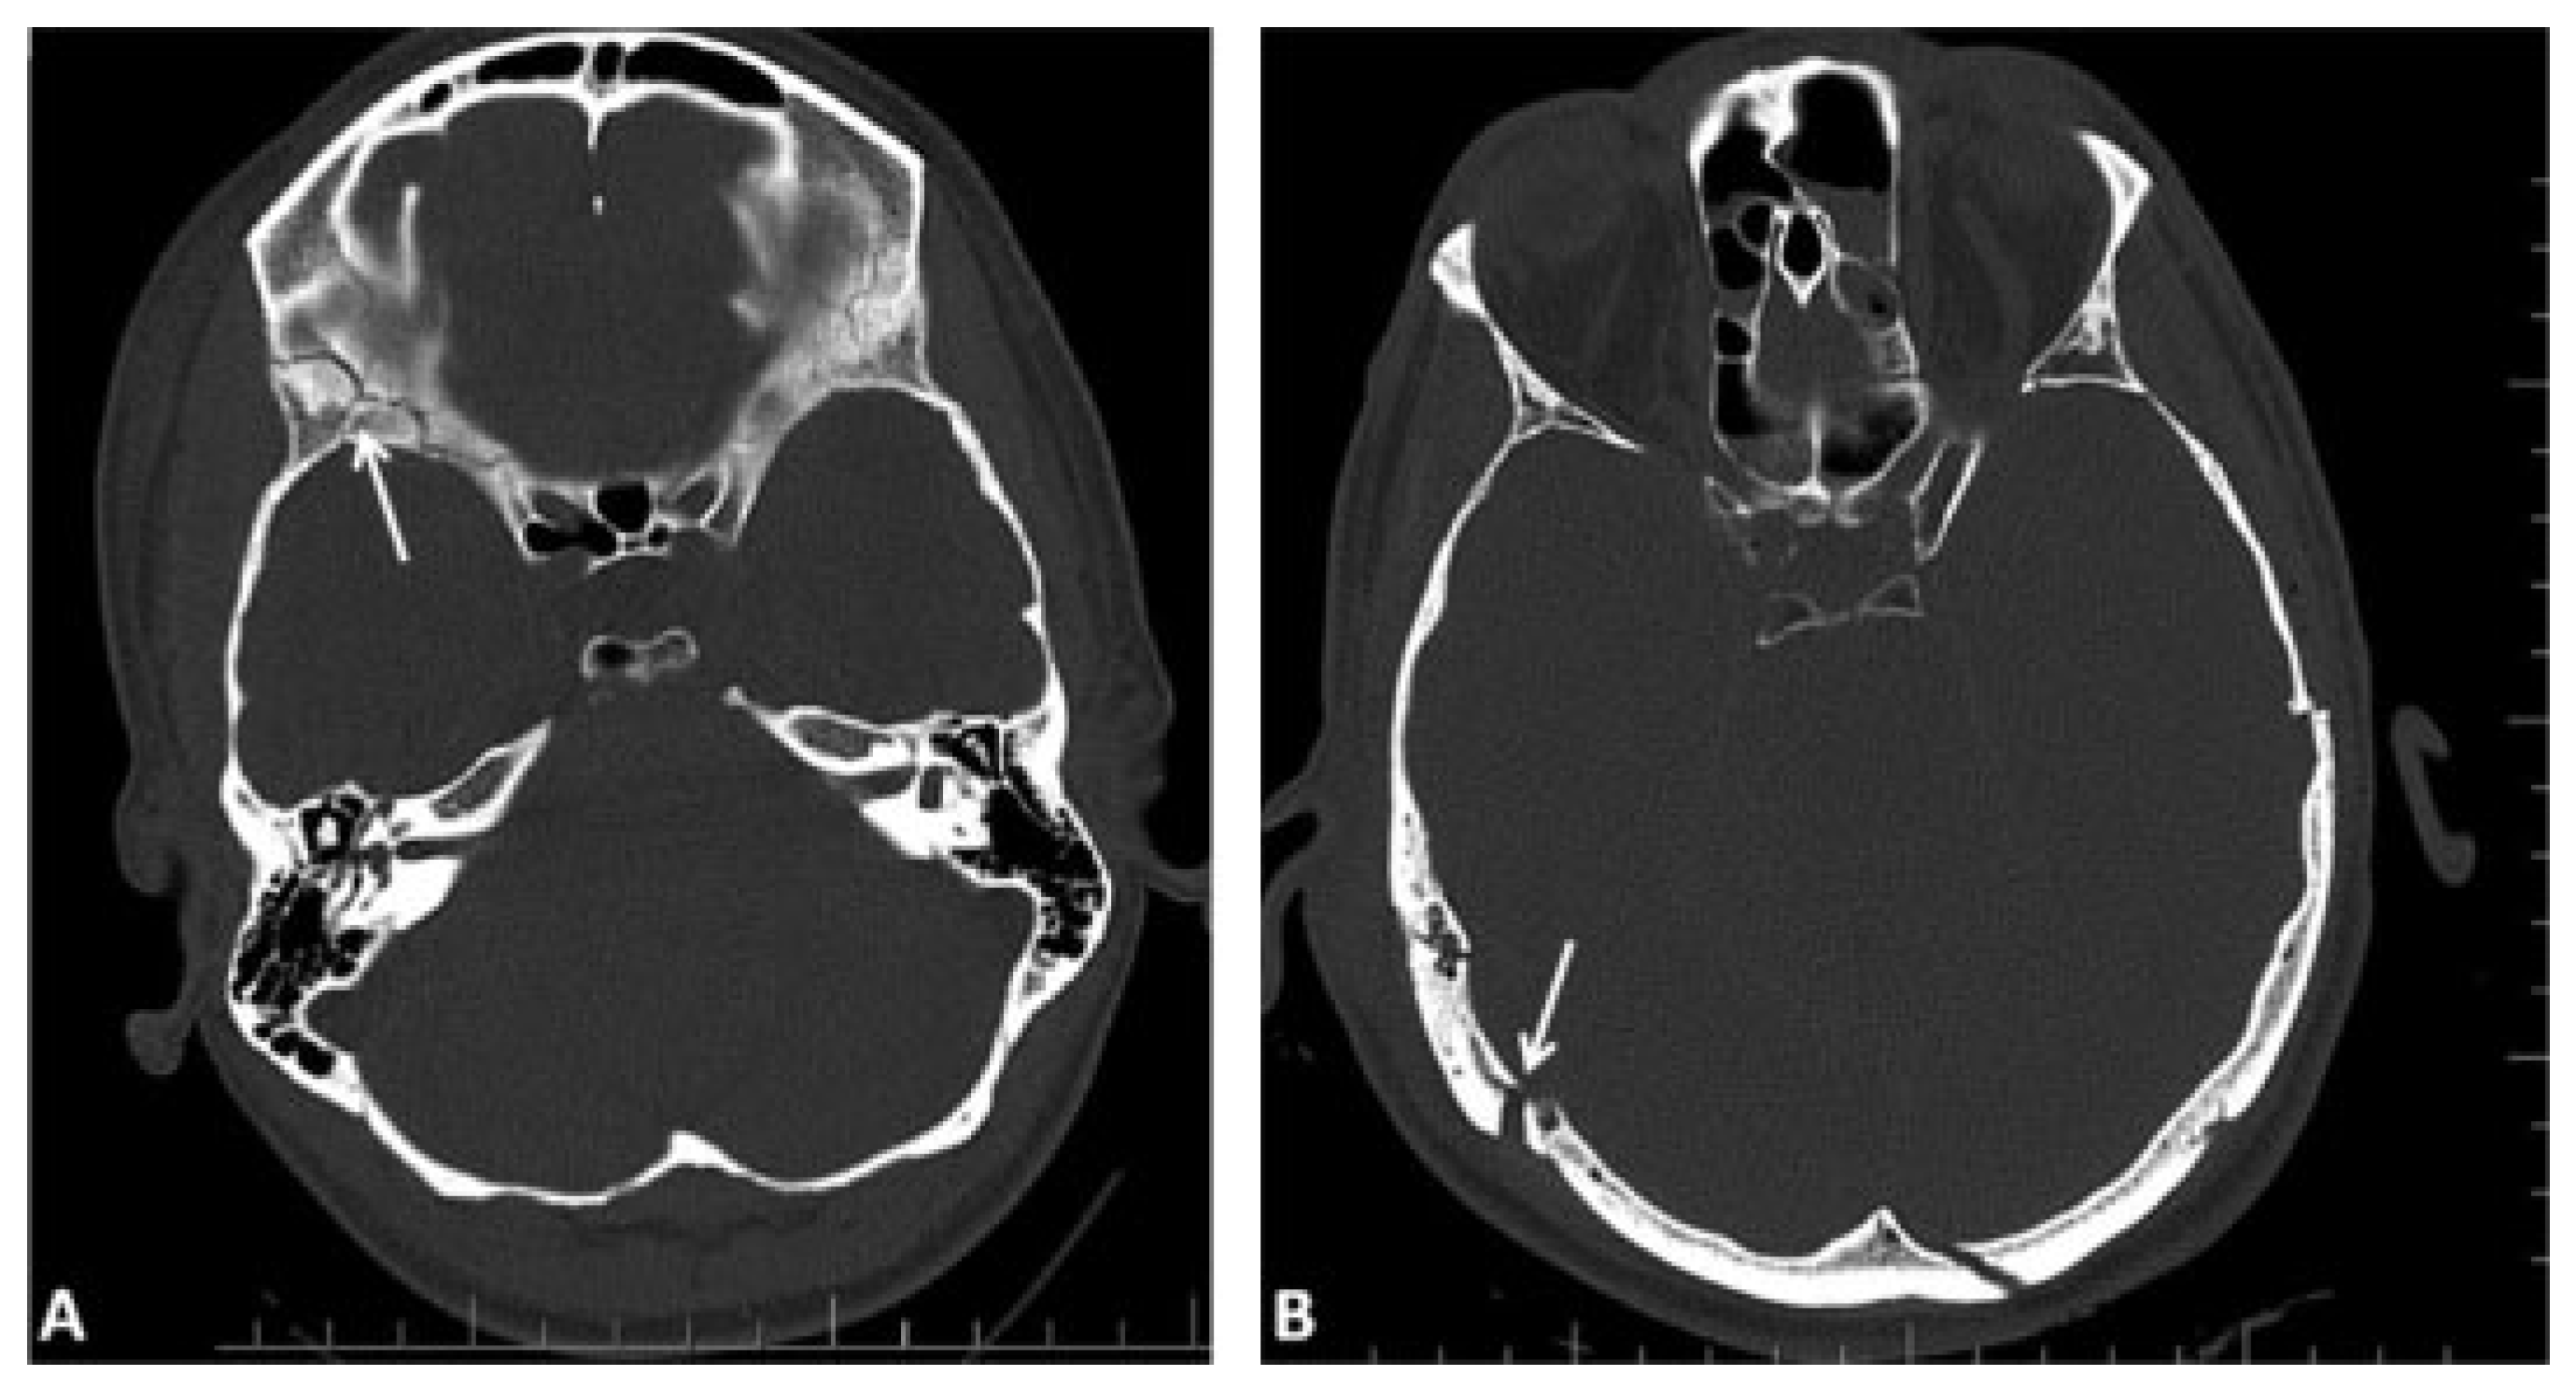

A list of clinically relevant intracranial features that may be associated with skull base and/or cranial vault fractures is proposed in addition to the fracture classification system to support the diagnosis and decision process (Table 2). These features include the presence of intracranial air (0 = none, 1 = single, or multiple air bubbles [up to 3 mm diameter], 2 = pneumocephalus [larger air pockets > 3mm]) (Figure 4B–D), intracranial mass lesion (epidural, subdural, subarachnoid, intraventricular, and/or intraparenchymal hematoma, brain contusions, foreign bodies) (Figure 4E–H), as well as radiological or clinical evidence of dural rupture, with following cerebrospinal fluid (CSF) leak.

Figure 4. Examples of associated diagnostic features with skull base and cranial vault fractures. (A) Partial opacification in the sphenoid sinus with air–fluid level in computed tomographic imaging (representing possible the presence of blood or fluid). (B–D) Presence of intracranial air: single or multiple air-bubbles in the subdural spaces (arrows in B) or in the subarachnoid space (arrow in C); (D) pneumocephalus. (E–H) Intracranial mass lesions: (E) epidural hematoma in the left occipital region (arrowheads) with small mixed (epidural and subdural) hematoma in the right temporal region (arrows), (F) subdural hematoma of the right hemisphere (arrows) with extension along the falx (arrowhead), (G) intraventricular haematoma, (H) brain contusions.